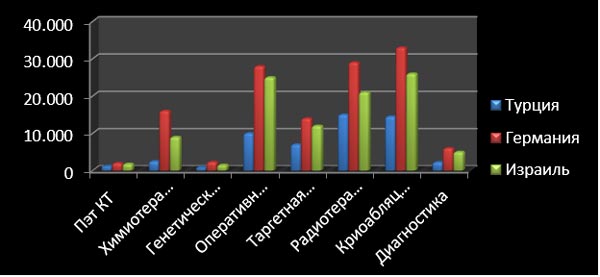

Порівняльна таблиця вартості лікування та обстеження

| Найменування послуги | Німеччина | Ізраїль | Туреччина |

| діагностика | від 1.200евро | 3500-6700Дол | 2250Дол |

| ПЭТ / КТ | 1900 евро | 1800Дол | 1200Дол |

| генетичний тест | 2300евро | 1500дол | 850Дол |

| хіміотерапія | 16000Дол | 9000дол | 2500дол |

| таргетна терапія | 14000Дол | 12000Дол | 7000Дол |

| оперативне лікування | 28000Дол | 25000Дол | 10000Дол |

| Лікування гострого лейкозу, включаючи підготовчий курс хіміотерапії, трансплантацію кісткового мозку | $425 000 | $250 000 | $70000-180000 |

| Лікування радіоактивним йодом | 9000евро | 6300Дол | 3000Дол |

| радіотерапія | 29000евро | 21000Дол | 15000Дол |

| Кріоабляція | 33000евро | 26000Дол | 14500Дол |

| Послуги супроводу перекладача, за годину | 30 – 40 евро | Не вимагає додаткової оплати | |

| Послуги письмового перекладу медичного тексту

(виписки, результатів досліджень і т.д) на російську мову. |

25 євро сторінка А4 (приблизно 1800 знаків) | $ 250 включаючи усні послуги перекладача | Не вимагає додаткової оплати |

| Транспортні послуги | за км 1,3 євро | Трансфер аеропорт клініка аеропорт 250Дол | Транспортні послуги не вимагають додаткової оплати |